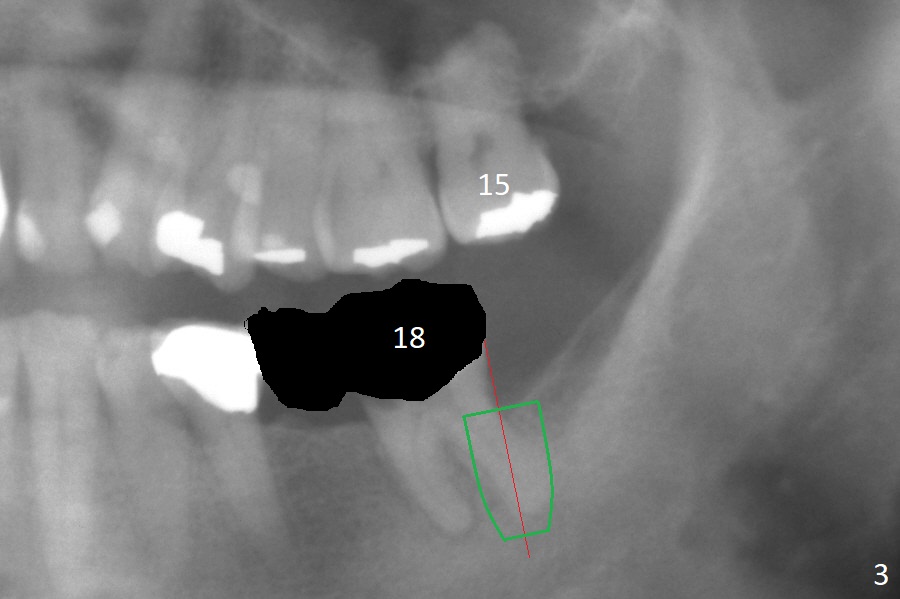

After extraction of the residual root at #18 (Fig.1), the septum is narrow, while the distal socket seems to be the most appropriate site for implant placement (Fig.2 (M: mesial)). In fact the implant needs to tilt slightly distally (relative to the original trajectory of the distal socket, Fig.3 green) to occlude with the opposing tooth. The implant at #19 could be placed more mesially (Fig.4 (*: Vera Graft)).